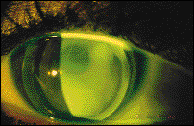

Fluorescein pattern of the PMMA rigid lens.